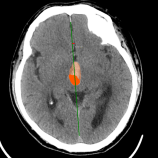

Chẩn đoán hình ảnh mô mềm tiên tiến cho vùng bụng.

Tăng cường độ tương phản I-ốt.

Hỗ trợ đánh giá an toàn cho bệnh nhân.

Đảm bảo hình ảnh chất lượng cao.